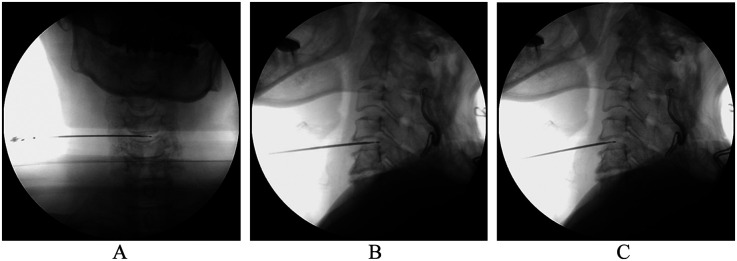

Background: The best treatment yielding clinical benefits was still equivocal and controversial for the treatment of cervical radicular pain (CRP). This study aimed to propose a novel combination strategy of percutaneous cervical nucleoplasty (PCN) and ultrasound-guided pulsed radiofrequency (PRF) of cervical nerve root for CRP, and to compare its therapeutic effects with PRF alone.

Methods: 120 CRP patients who satisfied the inclusion requirements between January 2016 and March 2019 were retrospectively analyzed and split into PCN + PRF and PRF groups. The propensity score matching (PSM) technique was used to correct the imbalanced confounding variables between the groups. Then, clinical outcomes including the visual analog scale (VAS) score, Neck Disability Index (NDI) score, clinical assessment scale for cervical spondylosis (CASCS), modified MacNab criteria, radiological parameters, and complications were evaluated.

Conclusion: We present and describe a novel strategy for the combined treatment of CRP in chronic cervical radicular pain using ultrasound-guided percutaneous disc radiofrequency ablation PCN and spinal nerve root pulse radiofrequency PRF, which is both effective and safe throughout the treatment process, reducing pain and improving function.